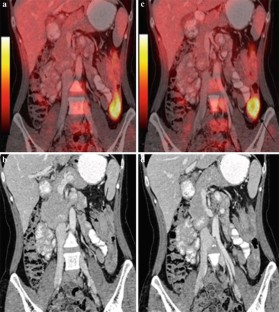

18F-FDG PET/CT in inflammatory pseudotumor of the colon causing intussusception

Inflammatory pseudotumor is a rare benign lesion mimicking malignancy both clinically and radiologically. An accurate diagnosis is still difficult and is based on the histological examination. Since inflammatory pseudotumor is exceptionally rare in the colon, this unexpected lesion can be mistaken for malignancy. We report the first case of inflammatory pseudotumor in the colon that showed 18F-fluorodeoxyglucose (FDG) uptake and acted as the lead point causing colocolic intussusception.

Fig. 1